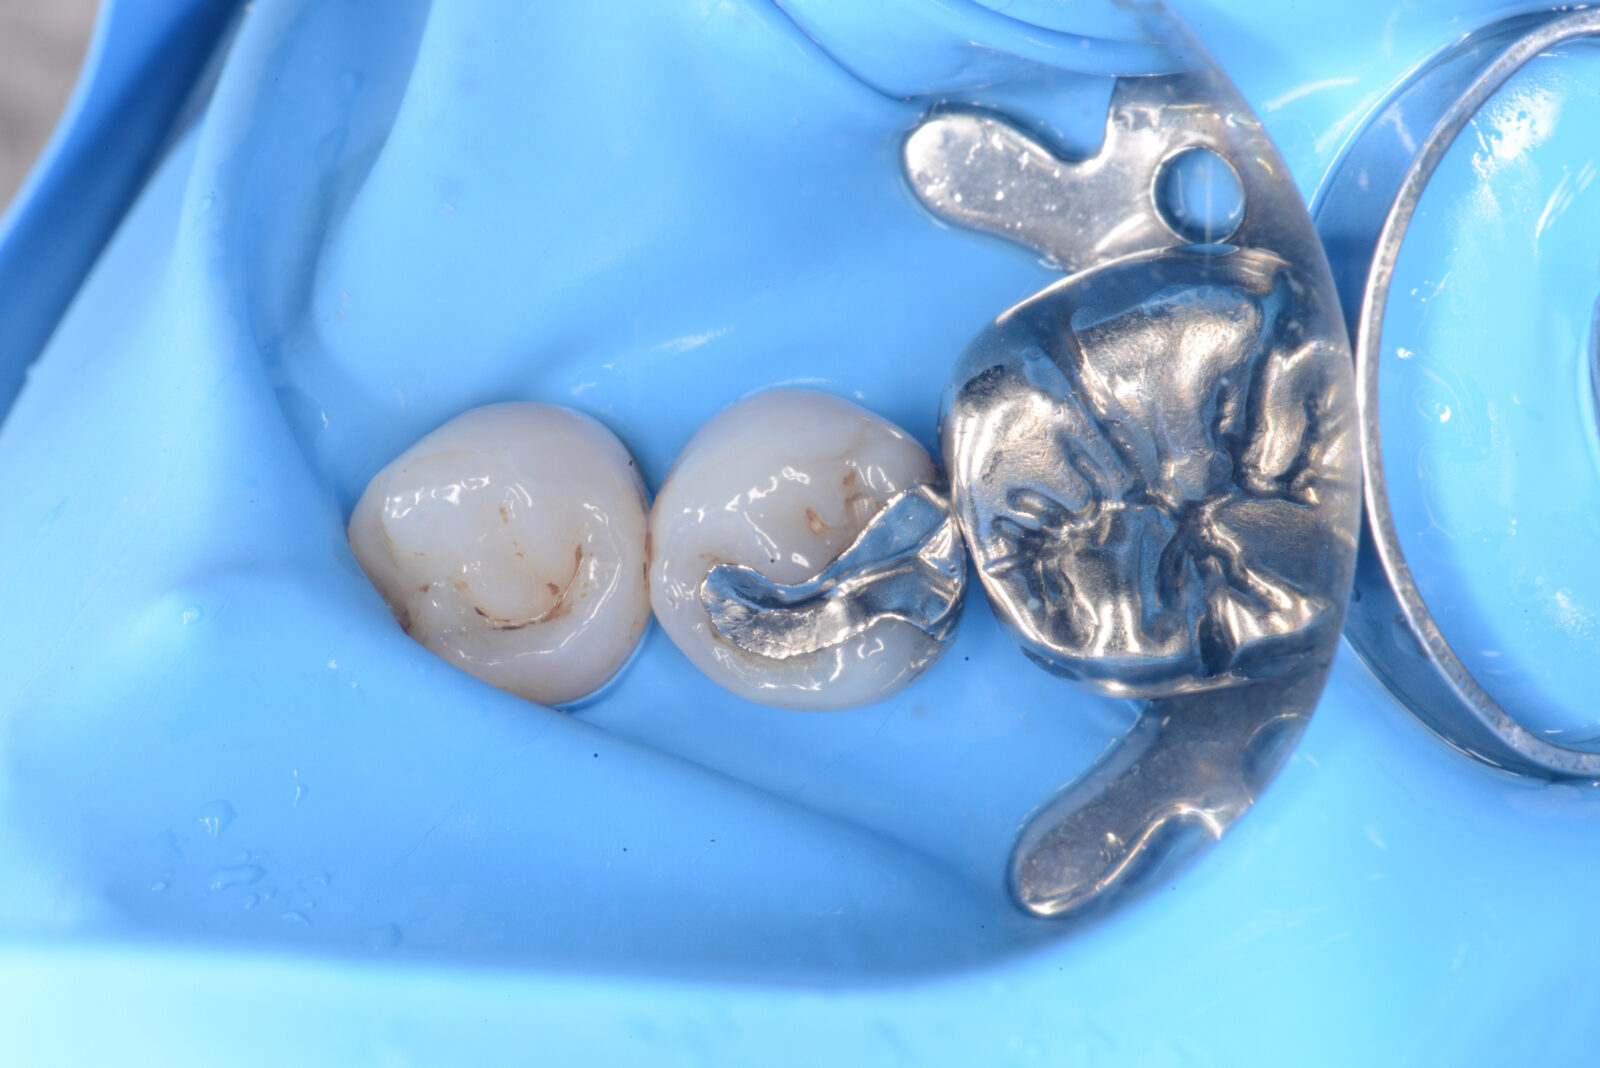

右下7ダイレクトボンディング

虫歯の治療希望で、右下の旧充填物と感染歯質の除去。 ラバーダム下で、プラークアウトと歯面処理を行い、接着操作とレジン充填を行った。 咬合調整はほぼなく研磨で終了。